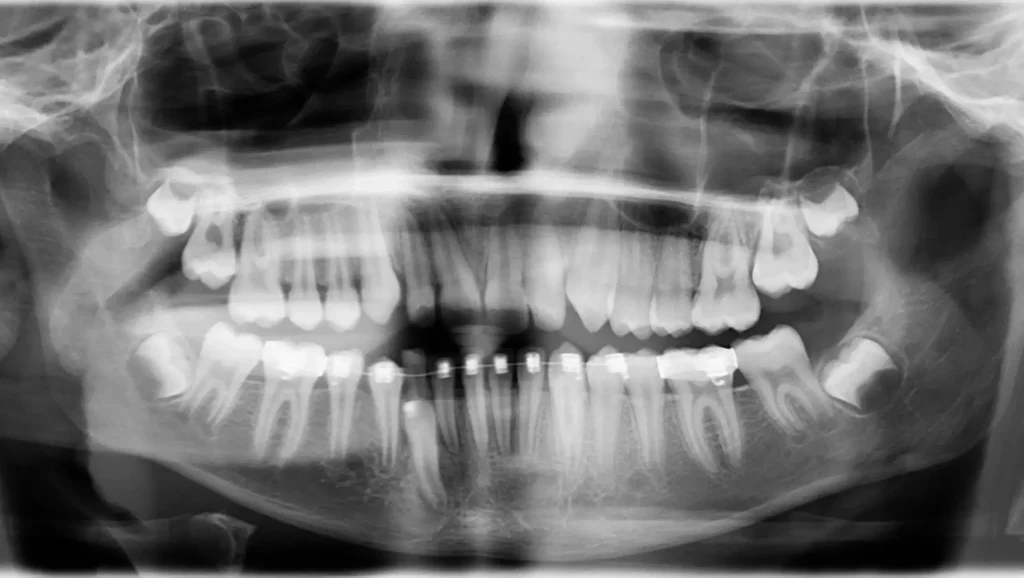

La evaluación final mediante radiografía y exploración clínica mostró los siguientes logros:

Canino impactado:

2- Alineación dental:

3- Relación oclusal:

4- Estética:

Este caso clínico demuestra la eficacia de un enfoque interdisciplinario para el tratamiento de ortodoncia de un canino impactado. La combinación de procedimientos quirúrgicos y ortodónticos permitió obtener resultados altamente satisfactorios. Este caso resalta la importancia de una planificación minuciosa y un seguimiento continuo para manejar con éxito situaciones complejas en ortodoncia.